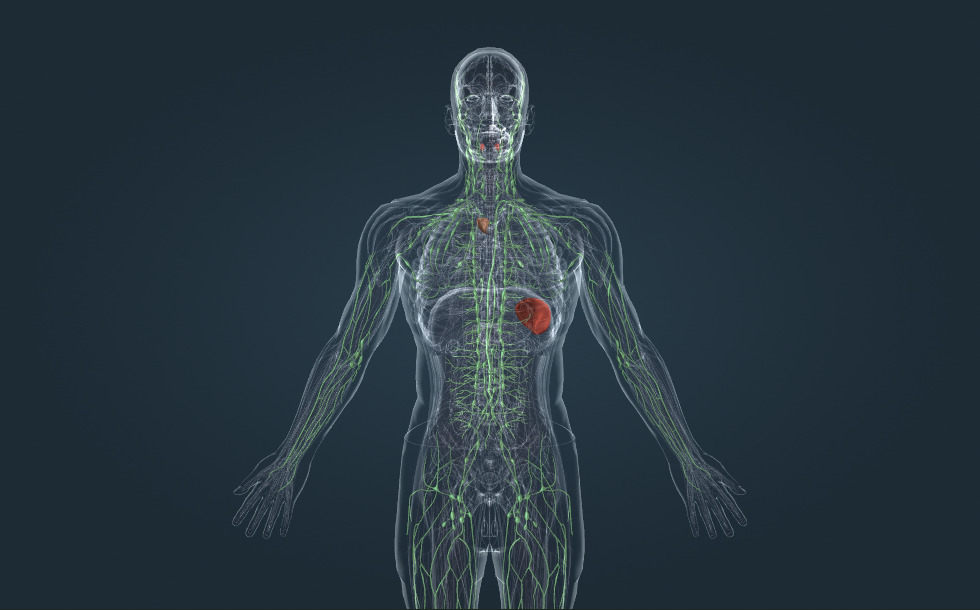

Lymfatisch systeem

- keelamandel

- milt - Speelt een belangrijke rol bij de groei van witte bloedcellen en de werking van het immuunsysteem.

- thymus - Speelt een belangrijke rol bij de groei van witte bloedcellen en de werking van het immuunsysteem.

- lymfeklier - Speelt een belangrijke rol bij de groei van witte bloedcellen en de werking van het immuunsysteem.

- thoracaal kanaal - Wordt afgevoerd in de linkerondersleutelbeenader waarbij het lymfe gemengd wordt met het bloed en wordt getransporteerd naar het hart.

- lymfevat

Lymfe is de vloeistof die terugvindt in de ruimte tussen weefsels. Het wordt geproduceerd via het bloed, door osmose door de wanden van de haarvaten heen. Metabolische producten worden afgevoerd in het lymfe. Lymfe wordt getransporteerd door de ondersleutelbeenader door lymfevaten. Daarnaast stroomt het ook door de lymfeklieren. Pathogenen die in het lymfe worden getransporteerd worden bestreden door witte bloedcellen in de lymfeklieren, wat een belangrijke rol speelt in het immuunsysteem. Andere belangrijke lymfatische organen omvatten de zweverik, de milt en de amandelen: ze spelen een belangrijke rol bij de groei van witte bloedcellen en het immuunsysteem.

Lymfe is de vloeistof die terugvindt in de ruimte tussen weefsels. Het wordt geproduceerd via het bloed, door osmose door de wanden van de haarvaten heen. Metabolische producten worden afgevoerd in het lymfe. Lymfe wordt getransporteerd door de ondersleutelbeenader door lymfevaten. Daarnaast stroomt het ook door de lymfeklieren. Pathogenen die in het lymfe worden getransporteerd worden bestreden door witte bloedcellen in de lymfeklieren, wat een belangrijke rol speelt in het immuunsysteem. Andere belangrijke lymfatische organen omvatten de zweverik, de milt en de amandelen: ze spelen een belangrijke rol bij de groei van witte bloedcellen en het immuunsysteem.